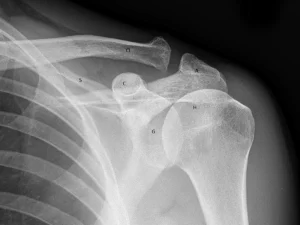

جااندازی باز و فیکساسیون دررفتگی مفصل آکرومیوکلاویکولار یکی از روشهای اصلی درمانی در مواردی است که آسیب شانه شدید بوده و روشهای غیرجراحی پاسخ مناسبی